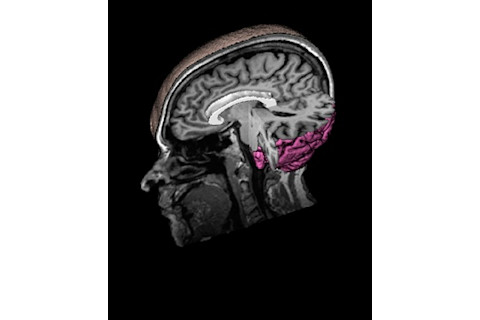

Picture of the Past Grandin’s left medial temporal lobe—involved in memory—appears in pink in this MRI. The white crescent is her corpus collosum, a bundle of fibers that connects the two hemispheres of her brain. MRI: Jason Cooperrider

Her brain is equally remarkable, according to a team of neuroimaging experts who study brain changes in autism at the University of Utah. Neuroscientist Jason Cooperrider and colleagues scanned Grandin’s brain using three different methods: high-resolution magnetic resonance imaging (MRI), which captures the structure of the brain; diffusion tensor imaging (DTI), a method to trace the connections between brain regions; and functional MRI, which indicates brain activity. The images reveal an unusual neural landscape that reflects Grandin’s deficits and talents.